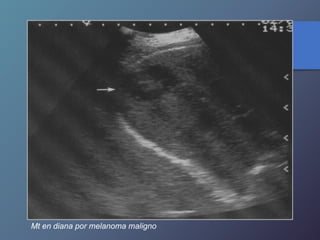

Mt en diana por melanoma maligno

Mt en dianapor melanoma maligno

MT en diana:

• Presentan una zona hipoecoica periférica, con centro

hiperecoico.

• Frecuente en carcinomas broncogenos.